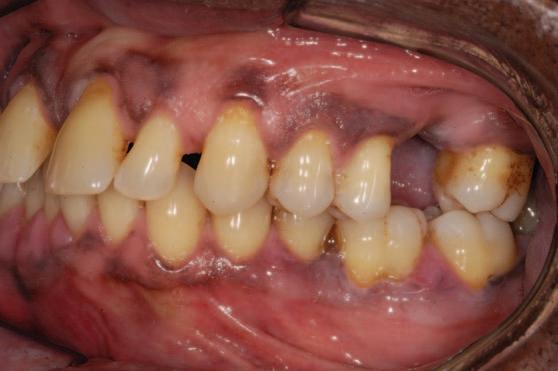

2. Wright, J.T., Crall, J.J., Fontana, M., Gillette, E.J., Nový, B.B., Dhar, V., et al Evidencebased clinical practice guideline for the use of pit-and-fissure sealants: a report of the American Dental Association and the American Academy of Pediatric Dentistry. J Am Dent Assoc 2016; 147 (8): 672-682.e12.

3. Lygidakis, N.A., Garot, E., Somani, C., Taylor, G.D., Rouas, P., Wong, F.S.L. Best clinical practice guidance for clinicians dealing with children presenting with molar-incisorhypomineralisation (MIH): an updated European Academy of Paediatric Dentistry policy document. Eur Arch Paediatr Dent 2022; 23 (1): 3-21.

4. Frencken, J.E. The state-of-the-art of ART sealants. Dent Update 2014; 41 (2): 119-120, 122-124.

CLINICAL TIPS